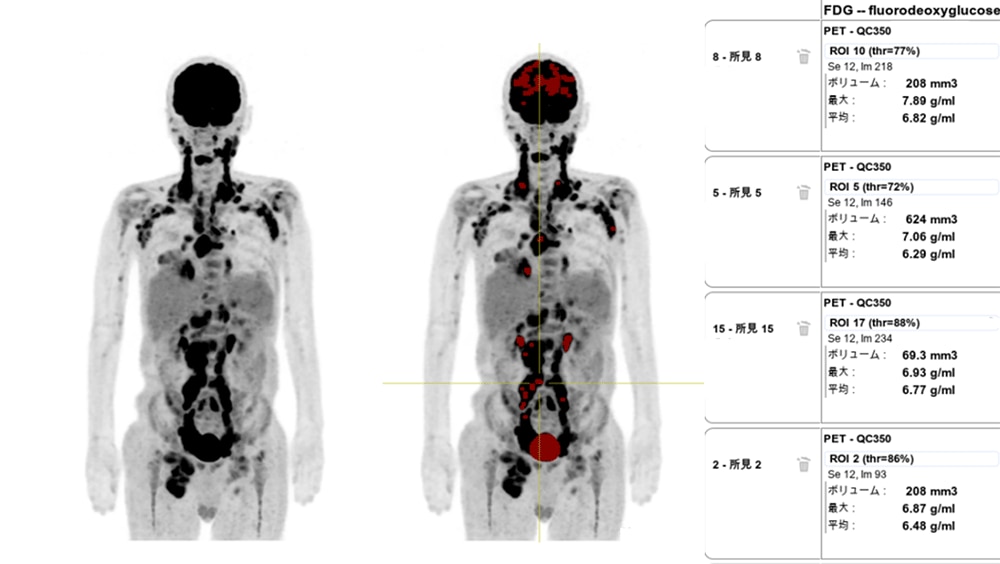

悪性リンパ腫や多発骨転移においてSUVが一番高い集積を見つけるのにPET VCARの多病変検出機能を利用しています。PET VCARでは病変を抽出するためのSUV閾値とその適応範囲を設定することによって、複数の病変を自動で抽出してきてくれます。最終的にサマリーテーブルを使用することで、複数のVOIの中で最もSUVが高い病変をすぐに確認出来るようになりました。この機能により、多病変の症例においてSUV測定が簡便になりました。

以前使用していたビューワーでは高い集積を複数箇所手動でSUV測定をし、その中でSUVが最大の集積を読影レポートに記載していました。この場合は多くの時間がかかっていましたが、PET VCARを使用することによって読影効率が向上しました。多いときには1日1例程度、悪性リンパ腫の症例があるので、日々有効活用しています。

50代 男性 悪性リンパ腫:治療前の病期診断のためFDG-PET検査施行

任意の閾値以上のSUV(例 SUV>6.5)を抽出し、SUVの高い順にサマリーテーブルから確認可能